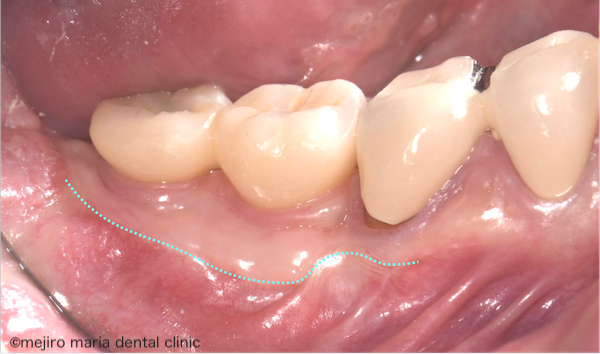

目白マリア歯科|歯周形成外科の症例|インプラントを守るための歯茎の移植(FGG)|治療前の歯茎の画像

術前の状態では、硬い付着歯肉と柔らかい可動粘膜の境界がかなりインプラントに近いのがわかると思います(写真はインプラントの最終的な上物が入る前の状態です)。

この状態でインプラントの上物が装着されると、柔らかい可動粘膜が歯磨きの際に動いてしまい、日々のブラッシングでしっかり汚れを落とすことが難しくなります。また、食事の際に粘膜が引っ張られインプラントと歯茎の間に汚れが流入しやすくなるというリスクも考えられます。

このように、付着歯肉が不十分な状態で最終的な上物を装着すると清掃性が確保できず、インプラントが歯周病に罹患するリスクが高くなり、インプラントを健康的に使用できる寿命が短くなってしまう可能性があります。

現状で1mm幅ほどしかない付着歯肉を少なくとも3mm幅ほどに増やすことが理想的です。